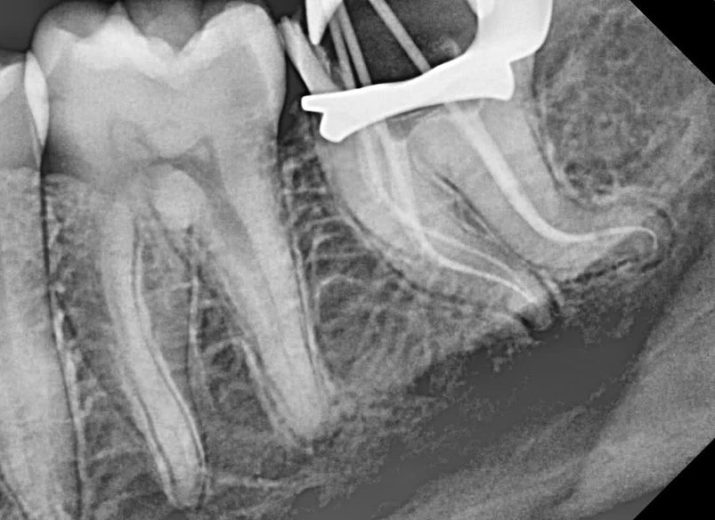

Severe curve:mandibular left second molar